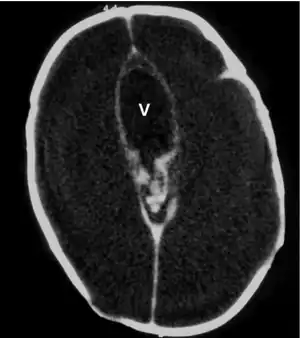

Macrocephaly is a condition in which circumference of the human head is abnormally large.[1] It may be pathological or harmless, and can be a familial genetic characteristic. People diagnosed with macrocephaly will receive further medical tests to determine whether the syndrome is accompanied by particular disorders. Those with benign or familial macrocephaly are considered to have megalencephaly.

Many people with abnormally large heads or large skulls are healthy, but macrocephaly may be pathological. Pathologic macrocephaly may be due to megalencephaly (enlarged brain), hydrocephalus (abnormally increased cerebrospinal fluid), cranial hyperostosis (bone overgrowth), and other conditions. Pathologic macrocephaly is called "syndromic", when it is associated with any other noteworthy condition, and "nonsyndromic" otherwise. Pathologic macrocephaly may be caused by congenital anatomic abnormalities, genetic conditions, or by environmental events.[3]

Macrocephaly is customarily diagnosed if head circumference is greater than two standard deviations (SDs) above the mean.[11] Relative macrocephaly occurs if the measure is less than two SDs above the mean, but is disproportionately above that when ethnicity and stature are considered. Diagnosis can be determined in utero or can be determined within 18–24 months after birth in some cases where head circumference tends to stabilize in infants.[12] Diagnosis in infants includes measuring the circumference of the child's head and comparing how significant it falls above the 97.5 percentile of children similar to their demographic. If falling above the 97.5th percentile then the patient will be checked to determine whether there is any intracranial pressure present and whether or not immediate surgery is needed.[2] If immediate surgery is not needed then further testing will be done to determine whether the patient has either macrocephaly or benign macrocephaly.

Benign macrocephaly can occur without reason or be inherited by one or both parents (in which it is considered benign familial macrocephaly and is considered megalencephaly form of macrocephaly). Diagnoses for familial macrocephaly is determined by measuring the head circumference of both parents and comparing it to the child's. Benign and familial macrocephaly is not associated with neurological disorders.[2] While benign and familial macrocephaly does not result in neurological disorders, neurodevelopment will still be assessed.